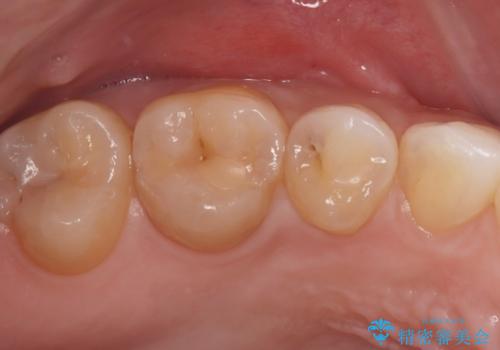

見逃しやすい小さな穴も精密に修復。自然な見た目のセラミックインレー

- 右上5番(小臼歯)の咬み合わせの面(咬合面)に小さな穴があることを主訴にご来院されました。視診およびレントゲン検査の結果、表面の穴は小さいものの、内部で虫歯が広がっていることが確認されました。患者様から「目立たないように治したい」というご希望があったため、健全な歯質を極力残しながら、審美性と耐久性に優れた**セラミックインレー(詰め物)**で修復する計画を立案しました。

治療ではまず、小さな穴から内部に広がっていた虫歯を、マイクロスコープ(歯科用顕微鏡)等を用いて精密に除去しました。虫歯を取り除いた後の空洞を整え、歯との適合性を高めるための精密な型取りを行いました。

後日、歯の色調に合わせてオーダーメイドで作製されたセラミックインレーを装着。セラミックは天然歯のような透明感があるため、修復した箇所がどこかわからないほど自然な仕上がりとなりました。